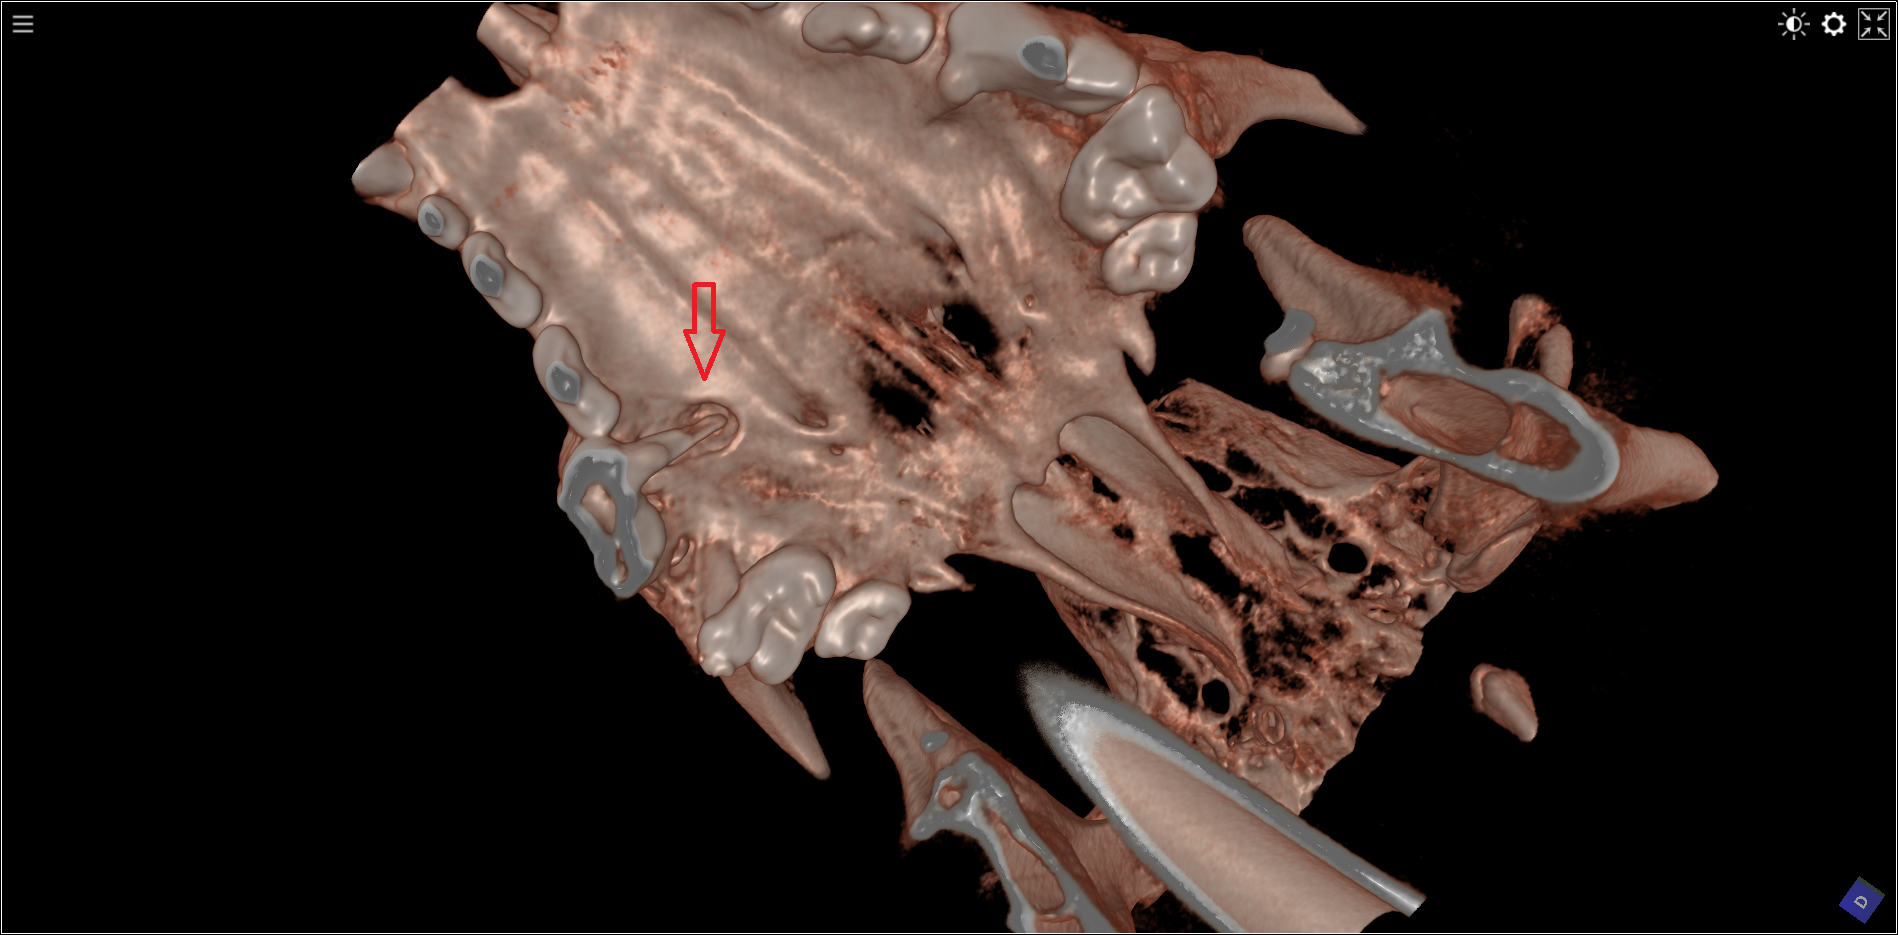

Tandverzorging bij de kat : opsporen van  aangetaste wortels en controle na verzorging